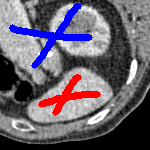

The motivation for this work comes from observing contradictions in using piecewise-constant intensity fitting terms in selective segmentation. Whilst good results are possible with this approach, the exceptional cases lead to severe limitations in practice. This is quite common in medical imaging as demonstrated in Fig. 1, where the target foreground has a low intensity. Given that the corresponding background includes large regions of low intensity, the optimal average intensities for this segmentation problem are and . For cases where , we see that by (1), almost everywhere in the domain . This means that it is very difficult to achieve an adequate result, without an over-reliance on the user input or parameter selection.

for and as defined in (33). This is consistent with respect to the intensities of the observed object and the concept of selective segmentation. In Fig. 3 we see the difference between CV and the proposed fitting terms for given user input on a CT image. For the CT image, the CV fitting terms are near 0 within the target region. This is despite there being a distinct homogeneous area with good contrast on the boundary. This illustrates the problem we are aiming to overcome. With the proposed fitting term this phenomenon should be avoided in cases like this. By defining as in (33) there is no contradiction if the foreground and background intensities of the target region are similar.